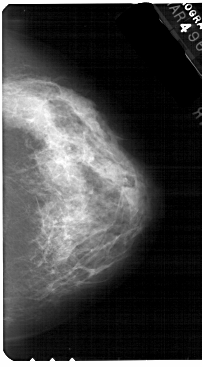

A_1559_1.RIGHT_MLO

RIGHT_MLO LINES 5491 PIXELS_PER_LINE 3301 BITS_PER_PIXEL 12 RESOLUTION 43.5 NON_OVERLAY